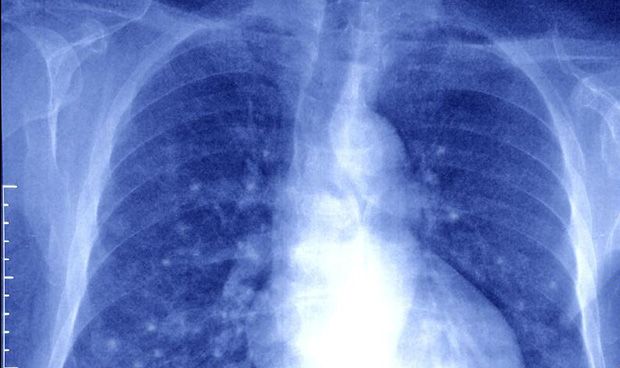

Una nueva técnica permite el diagnóstico precoz del cáncer de pulmón

Un nuevo sistema basado en biomarcadores epigenéticos para el diagnóstico precoz de cáncer de pulmón fiable, mínimamente invasivo y asequible permite ayudar a una detección más rápida de este tipo de tumor y, con ello, reducir las elevadas tasas de mortalidad actuales.

El de pulmón es la principal causa de mortalidad por cáncer en todo el mundo y la evolución del paciente está estrechamente vinculada a la etapa del tumor en el momento del diagnóstico.

Debido a su manifestación clínica tardía, la mayoría de los pacientes es diagnosticada en etapas avanzadas, cuando el tratamiento curativo ya no es posible. Actualmente, la citología es el método estándar para el diagnóstico de este tipo de cáncer en muestras respiratorias mínimamente invasivas, pero es un método con baja sensibilidad.